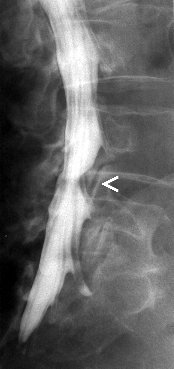

Myelografie is het in beeld brengen

van het ruggenmergkanaal door middel van een cotrasmiddel. Deze wordt

door middel van een punctie ingespoten in de duraal zak in de lage rug.

Er wordt dus in de rug geprikt zodat een naald door kan schuiven tussen

de wervels tot in het ruggenmergkanaal. Dit kan gebeuren onder

plaatselijke verdoving, maar dit is geen regel. Gesteld wordt dat er in

elk geval moet geprikt worden. Er kunnen opnames genomen worden ter

hoogte van de hals, borst of lage rug. Na de punctie worden er

conventionele opnames gemaakt waarna de patiënt naar de CT-scan

wordt gebracht om axiale beelden te maken in de regio waar zich

mogelijk problemen voordoen.

Het is echter zo dat deze onderzoek

steeds vaker vervangen wordt door een MRI vande rug, daar dit minder

invasief is, minder risicos inhoudt en beter verdragen wordt door de

patiënten.

Indicaties:

Het opsporen van een degeneratieve tussenwervelschijf |

Tumoraal proces tussen de wervels |

Trama met fractuur of verplaatsing van een wervel |

Post opperatieve problemen |